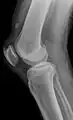

Operative image: 1. Kneecap 2. upper patella pole with drill holes 3. Stump of the quadriceps tendon